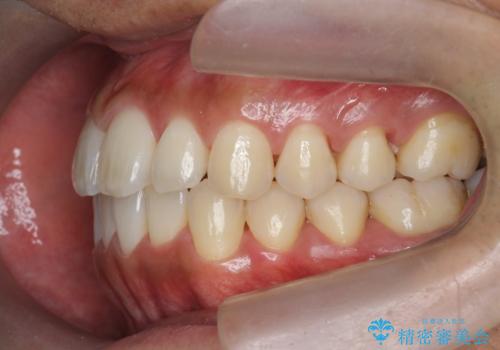

- 前歯のガタつきをきれいにしたい、と矯正治療を希望され来院されました。

マウスピース矯正インビザラインを用いてガタつきをきれいに並べていきます。

外側に傾斜していた前歯の角度も良くなり、「前歯の見た目が良くなった。」、と喜んでいただくことができました。